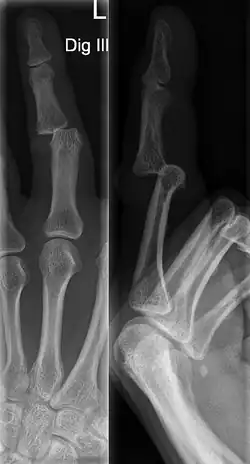

Diagnosis

A jammed finger can generally be diagnosed by a physical examination. Bone or joint deformity may indicate potential dislocations or fractures.[6] The basic structure of the finger includes three bones with joints in between each.[9] The joint closest to the tip is the distal interphalangeal (DIP) joint. The next joint, moving closer to the hand, is the proximal interphalangeal (PIP) joint. The thumb differs by only having two bones and one interphalangeal joint.[10]

The injured finger may be examined to determine where the pain is worst.[3] If the finger is sprained or dislocated, pain will be worse at the joint rather than the bone.[3] Due to the risk of dislocations or fractures, X-rays should be conducted prior to testing joint stability. This allows for prior detection of a dislocation or fracture.[3] It is recommended that a variety of views (lateral, oblique, and anteroposterior) are observed.[3] In extremely painful cases, a digital nerve block may be done to better assess the finger. This is where anesthetic is injected to either side of the base of the affected finger to reduce pain.[3]

DIP dislocations are much less common than PIP dislocations.[3] This is thought to be due to the increased stability of the DIP joint,[15] though not for certain.[2] Dislocations can be categorized based on the direction that the fingertip moves in relation to the knuckle.[6] If in the direction of the palm, it is a volar dislocation. If in the direction of the back of the hand, it is a dorsal dislocation.[6] If in the direction to either side, it is a lateral dislocation.[2] Of the three, dorsal dislocations are most common.[6] Dorsal dislocations of the PIP commonly lead to volar plate damage.[2]

Dislocations are often visually obvious due to joint deformity.[2] Therefore, x-rays may or may not be utilized in the diagnosis of a suspected dislocation. Though, they can provide feedback on post-reduction status if attempted prior to formal medical evaluation.[2] Dislocations may also be complicated by a tandem fracture.[5] These cases may necessitate a visit to a hand surgeon for surgery.[2]

Fractures are instances where the bone's structural integrity has been compromised.[20] If a jammed finger produces a fracture, pain will be greatest at the bone as opposed to the joint.[2] There may also be visual deformation of the bone itself.[6] As with any skeletal injury, an x-ray can be conducted to verify the presence of a fracture.[1] The distal phalanx is especially vulnerable to avulsion fractures.[1] These avulsion fractures are common following a first time dislocation of the DIP.[1]